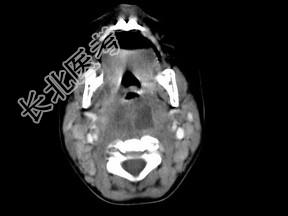

- 多项选择题10个月大的婴儿,发热, 曾患中耳炎,CT扫描如图所示, 正确的描述或诊断是 ( )

A、咽后壁软组织肿胀

B、其内密度不均

C、颈椎骨质未见明显异常

D、咽后壁脓肿

E、咽后壁寒性脓肿